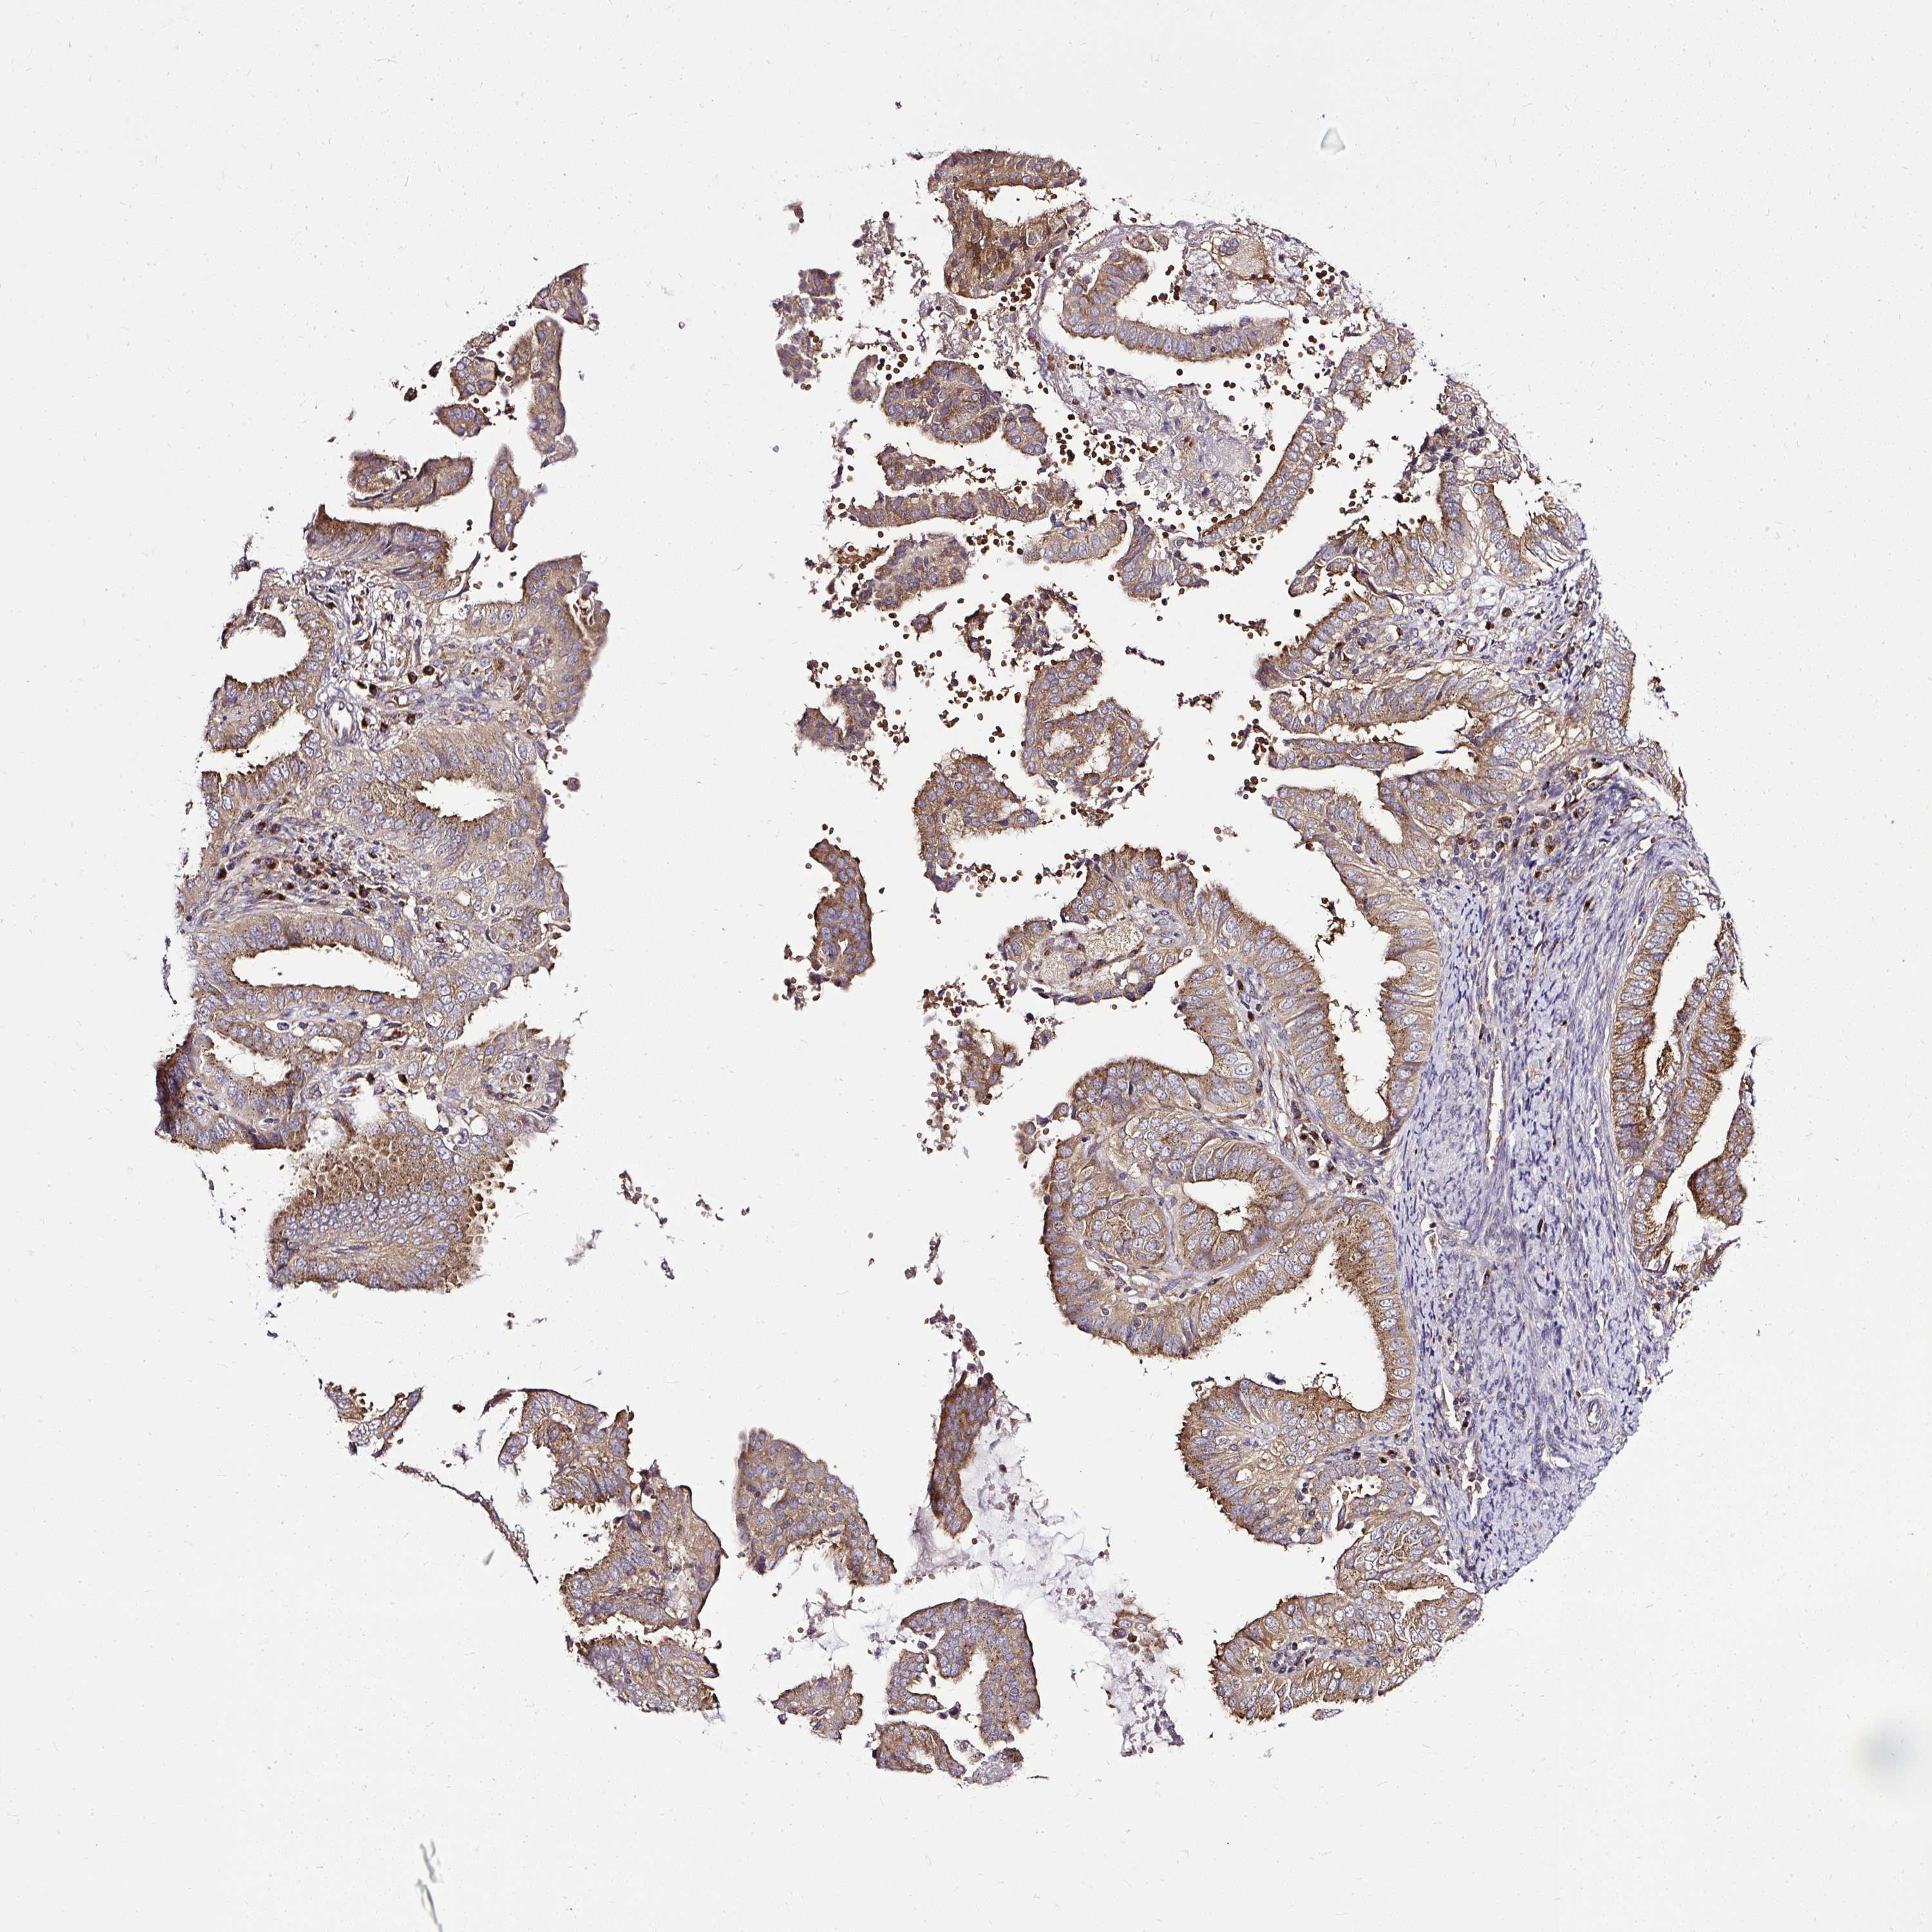

ENDOMETRIAL CANCER - Protein expressioni

A mouse-over function shows sample information and annotation data. Click on an image to view it in a full screen mode. Samples can be filtered based on level of antibody staining by selecting one or several of the following categories: high, medium, low and not detected. The assay and annotation is described here.

Note that samples used for immunohistochemistry by the Human Protein Atlas do not correspond to samples in the TCGA dataset.

Antibody stainingi

Antibody staining in the annotated cell types in the current human tissue is reported as not detected, low, medium, or high, based on conventional immunohistochemistry profiling in selected tissues. This score is based on the combination of the staining intensity and fraction of stained cells.

Each image is clickable and will lead to virtual microscopy that enables deeper exploration of all samples and also displays staining intensity scores, fraction scores and subcellular localization as well as patient and tissue information for each sample.

Antibody HPA029449

Antibody CAB055509

Staining

High

Medium

Low

Not detected

Intensity

Strong

Moderate

Weak

Negative

Quantity

>75%

75%-25%

<25%

None

Location

Nuclear

Cytoplasmic/membranous

Cytoplasmic/membranous,nuclear

Adenocarcinoma, NOS